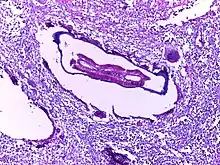

![]() | Filarial lymphadenitis | Micrograph showing section of an adult filarial worm. Surrounding tissue shows dense infiltration of eosinophils. | Category: Histopathology of filariases | filariasis |